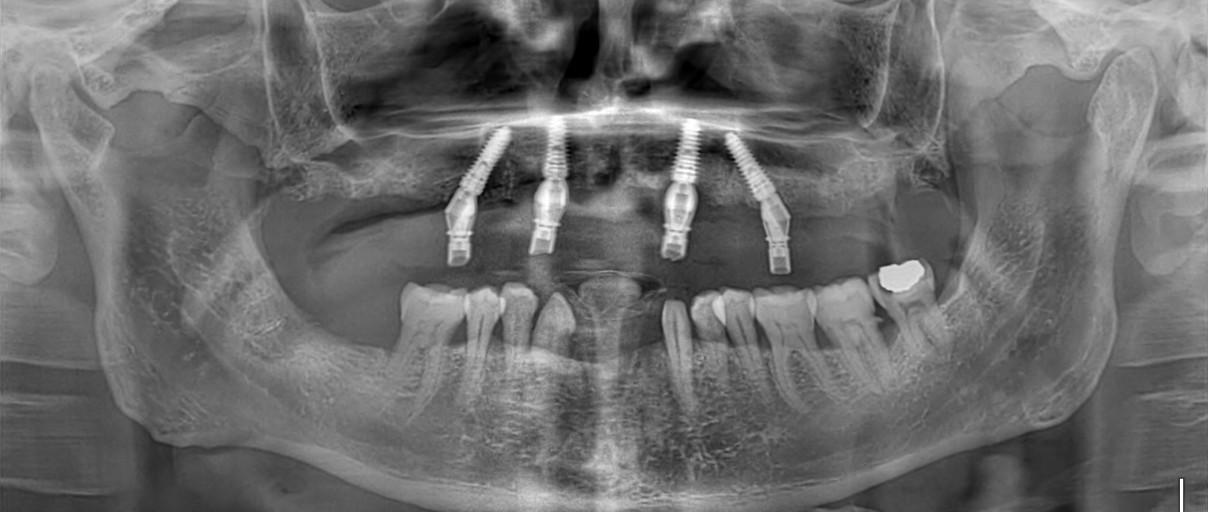

Immediate (Erken) Yükleme İmplant

mmediate (Erken) Yükleme İmplant, diş çekimi yapılan bölgeye çekim sonrası hemen veya kısa süre içinde implant yerleştirme işlemidir. Bu yöntem sayesinde çene kemiğinin korunması, tedavi süresinin kısalması ve estetik gülüşün hızlı sağlanması mümkün olur.

Batman’da Arya Dental Diş Kliniği’nde, erken yükleme implant işlemleri uzman hekimler tarafından modern cerrahi teknikler ve steril ortamda gerçekleştirilir. Hastalar genellikle tek seansta hem implant hem geçici protez ile işlemi tamamlayabilir.